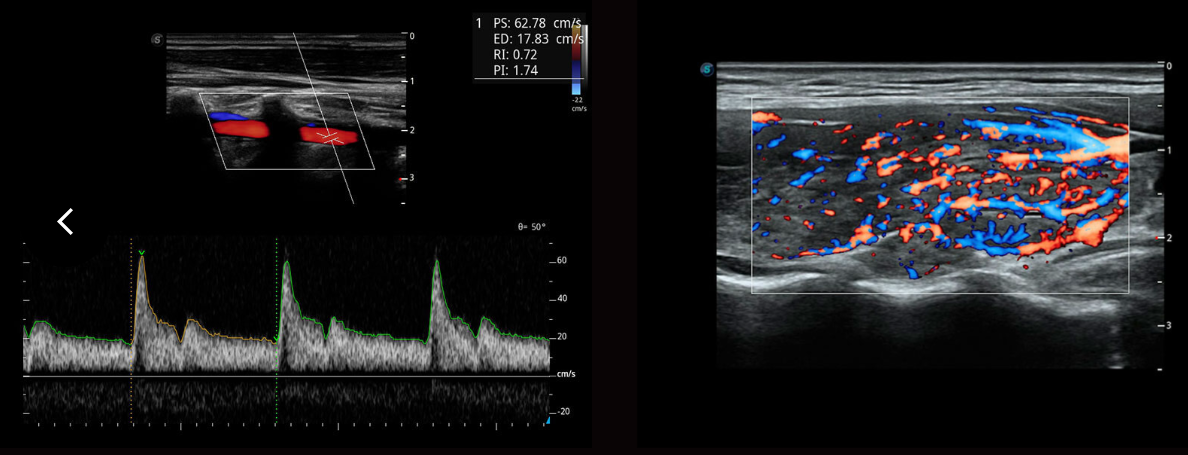

SR-Flow

Công nghệ lọc hiệu quả cao giúp hình ảnh hóa dòng chảy chậm, cho phép hiển thị Doppler sống động với độ nhạy cao.

Micro F ( siêu âm vi mạch)

Micro F cung cấp một phương pháp cải tiến để mở rộng phạm vi dòng chảy có thể nhìn thấy trong siêu âm, đặc biệt là để hình dung huyết động của các mạch máu nhỏ. Mang lại sự tự tin chẩn đoán cao hơn để đánh giá các tổn thương và khối u.

Bright Flow

Dòng chảy Doppler màu giống 3D giúp tăng cường khả năng xác định ranh giới của thành mạch mà không cần sử dụng đầu dò 3D. Đổi mới này giúp các bác sĩ hình dung trực quan hơn về lưu lượng dòng máu.